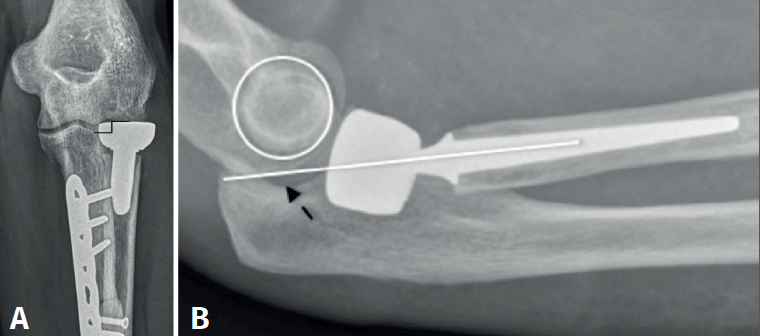

Radiológicamente, podemos cuantificar el exceso de longitud midiendo la distancia entre el margen lateral de la apófisis coronoides y el límite superior del implante, siendo posible apreciar esclerosis, geodas e irregularidad del capitellum. En casos de inestabilidad posterior secundaria al exceso de longitud, el eje longitudinal del radio será posterior al epicóndilo (drop sign) (Figura 2).

El exceso de longitud superior a 6 mm puede provocar pérdida de paralelismo de la articulación ulnohumeral, con ensanchamiento del lado lateral y estrechamiento del lado medial(6).